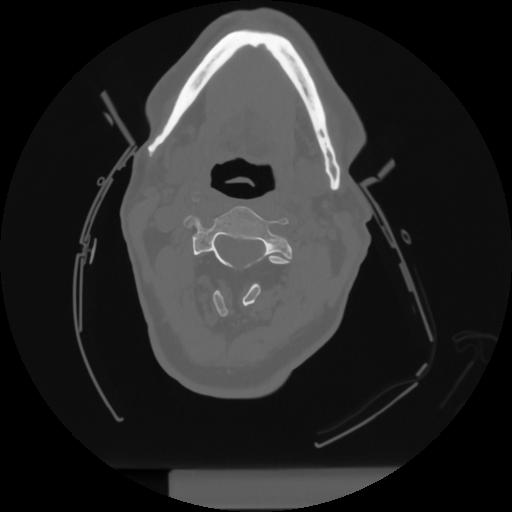

12 P.BLANDAS,,Vol,0.5,P.BLANDAS,,